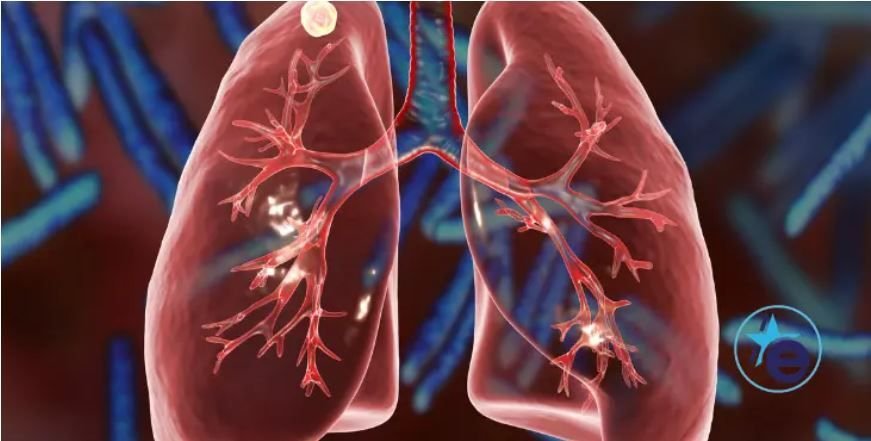

Las imágenes médicas de escáner in vivo y el estudio de las lesiones patológicas macroscópicas y de anatomía patológica de la frecuencia y gravedad de granulomas pulmonares demostraron una reducción significativa de la infección con la vacunación con MTBVAC.